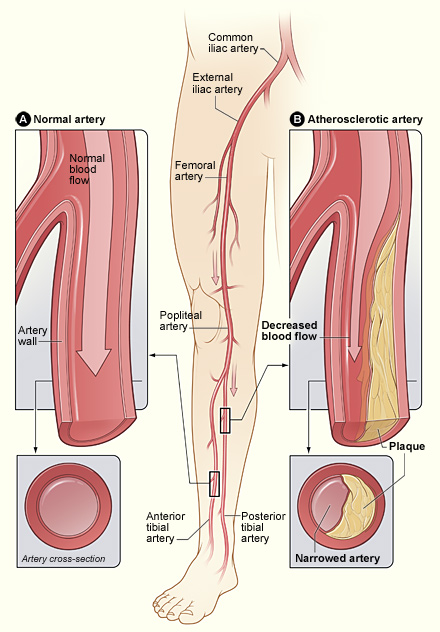

Value added benefits of the Coronary Angioplasty:

Value added benefits of the Angioplasty PTCA :

Value added benefits of the Renal Angioplasty:

Value added benefits of the Femoro Popliteal Bypass:

Value added benefits of the Popliteal Bypass or Extra Anatomic Bypass: